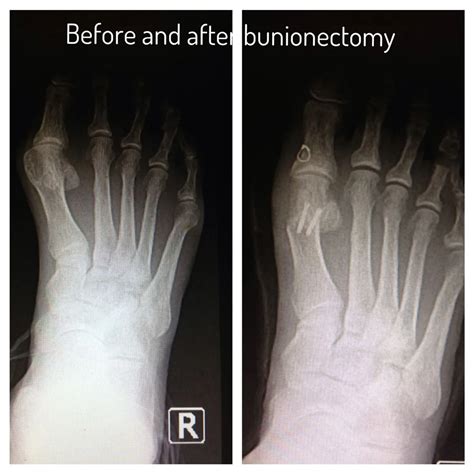

If the Bunion X Ray indicates a severe deformity, or if conservative treatments fail to provide relief, surgical correction may be proposed. Surgery aims to realign the metatarsal bone, remove the bony prominence, and stabilize the joint. Because the bone structure is unique to every patient, the X-ray is the most important tool for a surgeon to visualize the exact alignment needed to restore a pain-free gait.

• Surgical Planning: If surgery is required, the X-ray acts as a blueprint to determine which type of osteotomy or fusion is necessary.

• Measuring the Angle: Doctors measure the Hallux Valgus Angle (HVA) and the Intermetatarsal Angle (IMA) to quantify the severity of the bunion.